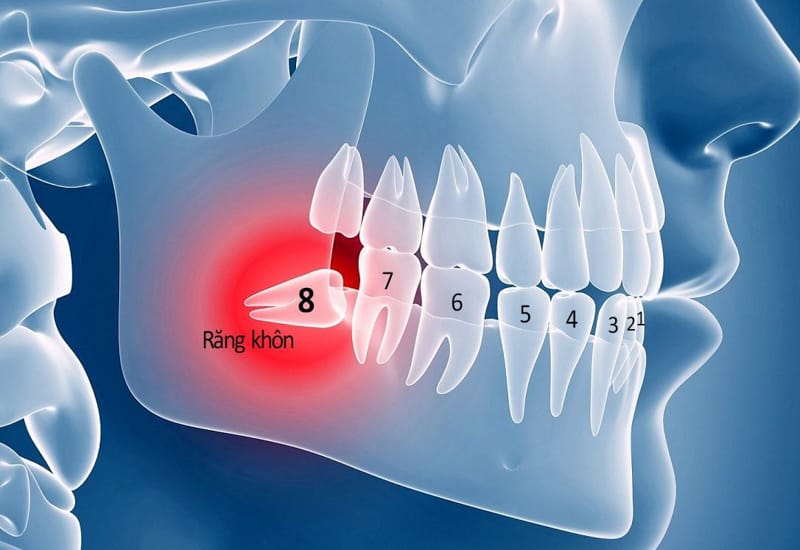

Tại nha khoa Navii, bác sĩ có chuyên môn cao sẽ trực tiếp thăm khám và nhổ răng khôn cho bạn. Có rất nhiều trường hợp răng khôn mọc ngầm, mọc lệch có thể gây ảnh hưởng tới dây thần kinh nếu không được khám và chụp chiếu cẩn thận. Do vậy, khi đến nha khoa Navii bạn sẽ không phải lo lắng về chất lượng dịch vụ và tay nghề bác sĩ tại đây